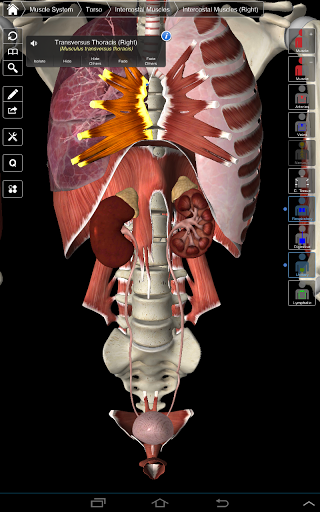

Essential Anatomy 3 reprezentuje najnowsze przełomowe technologie 3D i innowacyjny design. Najnowocześniejszy silnik graficzny 3D, zbudowany na zamówienie przez 3D4Medical od podstaw, zapewnia bardzo dokładny model anatomiczny i zapewnia doskonałą jakość grafiki, której żaden inny konkurent nie jest w stanie osiągnąć.

Aplikacja przedstawia unikalne podejście do uczenia się ogólnej anatomii. Grafika jest nieporównywalna i sprawia, że uczenie się, dzięki wykorzystaniu treści informacyjnej i innowacyjnych funkcji, jest bogatym i wciągającym doświadczeniem.

Ta aplikacja zawiera niezbędną anatomię dla 10 systemów:

⁃Muscles

⁃Tkanka łączna

⁃Żyły

⁃Artyki

⁃Nerwowość

NOWA TECHNOLOGIA 3D

Essential Anatomy 3 jest responsywny, wizualnie oszałamiający i pozbawiony wysiłku. Aplikacja jest w pełni 3D, co oznacza, że możesz zobaczyć dowolną strukturę anatomiczną w izolacji, a także pod dowolnym kątem.

Mądra funkcjonalność znajdująca się w aplikacji pozwala użytkownikowi usunąć warstwy mięśni za pomocą narzędzia "skalpela". Ta aplikacja zapewnia użytkownikom możliwość włączania / wyłączania systemów bez potrzeby wyłączania poszczególnych struktur lub pomieszania wielu predefiniowanych kart regionalnych, tak jak w przypadku innych aplikacji.

---- Ponad 4000 bardzo szczegółowych struktur anatomicznych